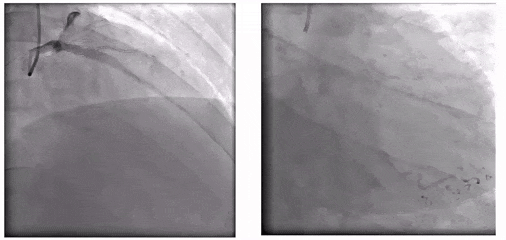

入院造影

冠状动脉造影显示,左冠脉整体状况尚可;右冠脉呈弥漫性严重病变,病变核心位于第二转折区,表现为典型血管编织样改变及多腔结构(至少两个假腔)。具体受累范围包括:(1)中远段弥漫性扩张伴血管分层;(2)第二转折后严重狭窄及继发的狭窄后扩张(累及PLA);(3)PDA全程弥漫性重度狭窄。结合患者症状持续+狭窄严重+真腔存在连通可能,决定再次行介入治疗。

左冠造影

右冠造影